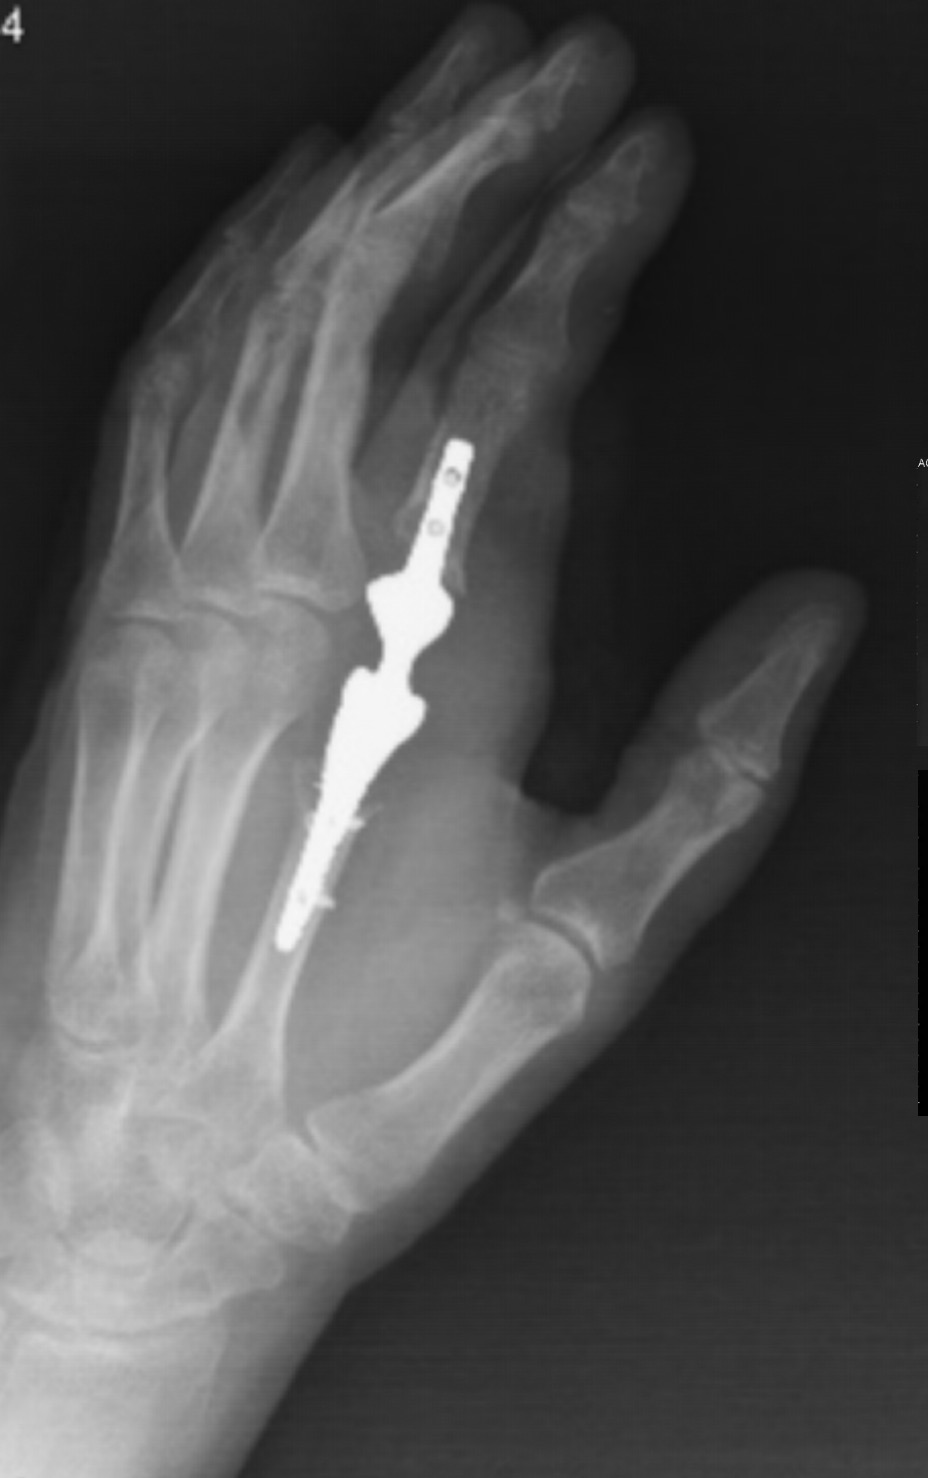

掌指 | 指间关节假体 价格:

产品特性:生物惰性钽金属:零排异,组织相容性极佳;仿生微孔:促骨长入与生物固定;精准解剖匹配:CT建模定制,贴合掌骨/指骨形态;力学仿生优化:弹性模量近指骨,防应力遮挡;表面耐磨涂层

适用症:晚期类风湿/骨关节炎致关节毁损;手部肿瘤切除后骨缺损重建;严重创伤性指关节塌陷或坏死